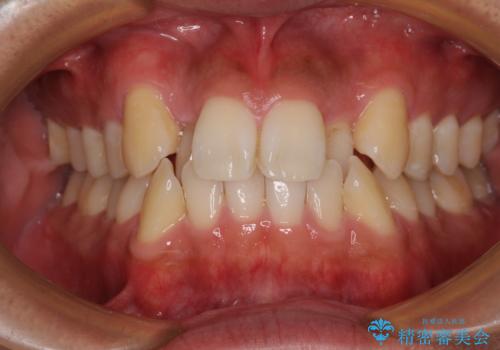

一年と数か月で矯正を終えることができました。

下顎前歯部には後戻り防止のワイヤーを装着しています。